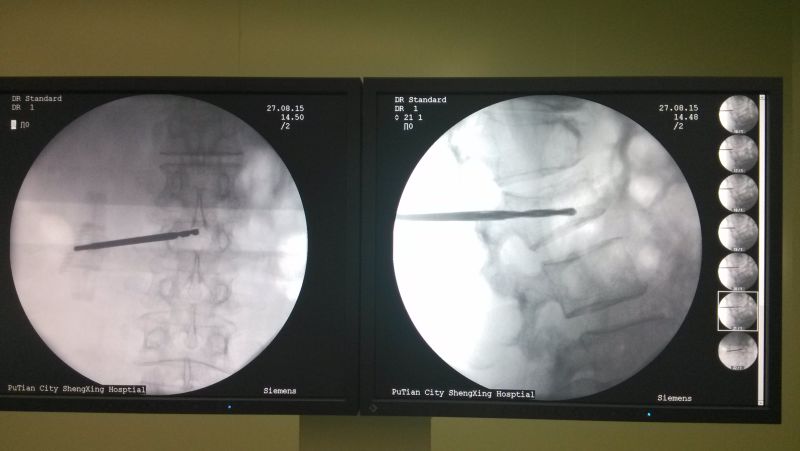

中醫(yī)科曹平主任組織全科醫(yī)生,對(duì)林阿婆的病情進(jìn)行討論、分析。認(rèn)為該病人可以采取“椎體成形術(shù)”進(jìn)行治療,精心制定了手術(shù)方案。8月27日,林阿婆被送入手術(shù)室,在林伯龍主治醫(yī)師的操作下,通過(guò)C型臂X光機(jī)透視定位,成功完成穿刺,并順利注入骨水泥。

術(shù)中透視